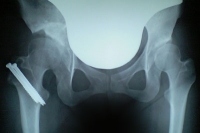

レントゲンとCTを撮影。

レントゲンを見ると、28日の時と大きな違いは(素人目には)見られませんでしたが、以前より着実に骨の癒着は良くなっているそうです。

そして独歩の許可が下り、術足に体重100%加重可能になりました。